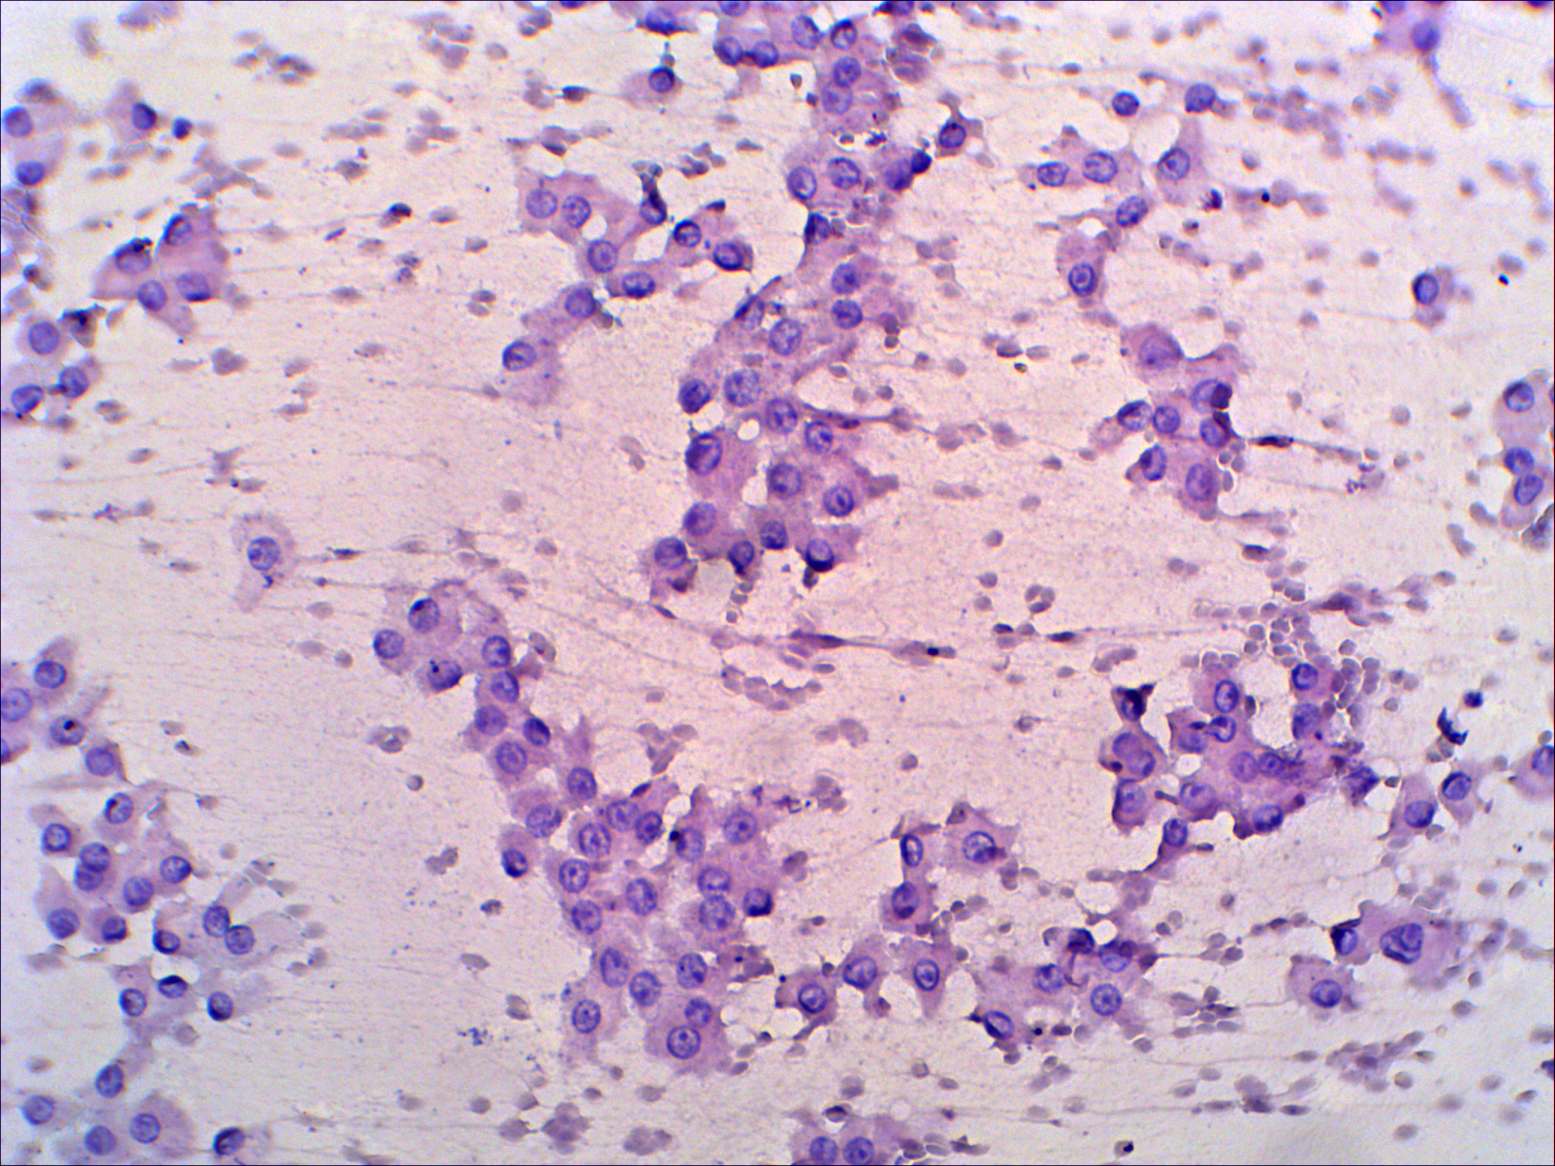

Thyroid cancers - case 262 (cytologic picture 2)

Pap-smear, 200x. Oxyphilic cells are in loose groups.